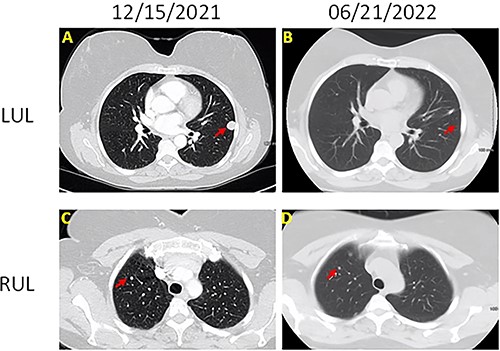

The patient was a 60-year-old female who presented with persistent shortness of breath for 1 year. Chest computed tomography (CT; Fig. 1) with contrast showed a 1.5-cm well-circumscribed, homogenous, noncalcified nodule in the left upper lobe and multiple similar, but smaller (3–5 mm), nodules involving right upper, right lower and left lower lobes. Positron emission tomography (PET)-CT revealed that the 1.5-cm nodule was hypermetabolic with SUV of 5.2 and suspicious for malignancy. The other smaller nodules were not detected by PET scan.

Chest CT images of the lesions (A) left upper lobe lesion (1.5 cm) before surgery on 15 December 2021; (B) left upper lobe lesion after surgery on 21 June 2022; (C) right upper lobe lesion (0.5 cm) on 15 December 2021; (B) right upper lobe lesion on 21 June 2022; there is no change on the size.